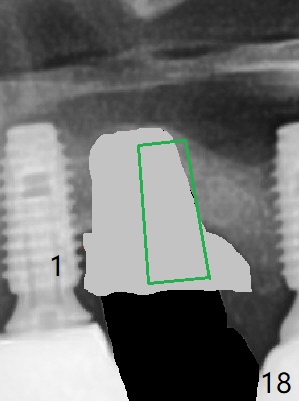

Periimplantitis develops with bone loss 4 years 5 months post cementation (Fig.15). It appears that the implant should be removed (Fig.16, unipost cemented with Ketac, prepare special screw driver after handpiece making a slot), followed by bone graft (Fig.17 red circles), particularly mesial to #1 implant and PRF. Prepare Titanium brush to clean the exposed implant threads of #1 implant. When the defect heals (with increased bone height, Fig.18 greyish area), place a smaller implant (green) with guide.